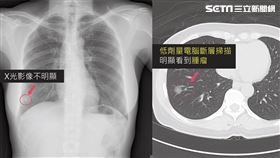

寶媽也中鏢!小心肺癌會玩「捉迷藏」

肺癌是國人癌症中的頭號殺手,無須贅述!肺癌之所以危險...

1/3肺癌患者沒咳嗽 小心這些症狀

提到肺癌的症狀,我們傾向馬上聯想到「咳嗽」,研究指出...